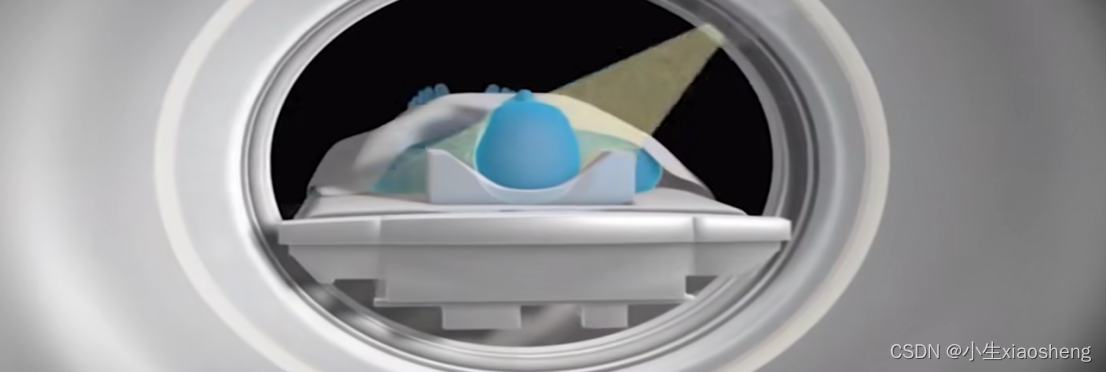

核磁共振:核指的就是人体中水的氢原子核,使用这个技术能让身体里的以氢原子为主体的原子核保持一定的规律排列,在这个过程中机器还会持续向身体发射射频脉冲,记录并对比检查部分和正常情况的器官存在那些差异,适合脑子、脊柱、脊髓、肌肉、脂肪,但不适合动的器官。